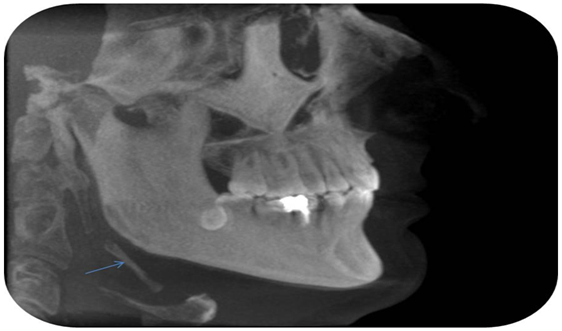

Case 2

The second case was an asymptomatic 44year old male patient who underwent a CT exam using multi-slice CT scanner (GE 16 light speed) for implant positioning assessment. The parameters used were helical, 0.625mm slice thickness, pitch 0.562:1, interval 0.625mm, 120Kv and 250mA. The images were obtained as Dicom file and reconstructed in 3D mode using the Unic 3D view program. This showed bilateral elongated styloid process. The right one is completely calcified and the left one partially calcified (Figure 4,5).

Figure 4 Complete calcification of the right ligament.

Figure 5 Partial calcification of the left ligament.